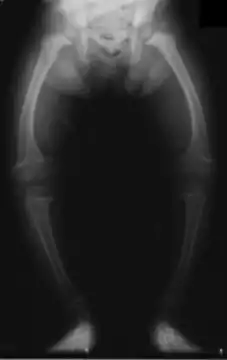

Рахіт уражає увесь скелет, але передусім ті кістки, які в цей період ростуть найбільш інтенсивно. За кістковими деформаціями можна робити висновок про час появи рахіту. Викривлення кісток голови виникає в перші 3 місяці життя, кісток тулуба і грудної клітки — через 3—6 місяців, кінцівок — у другому півріччі.

Після 6—8 місяців з'являються деформації кінцівок:

- а) «рахітичні браслетки», «нитки перлів», зумовлені потовщенням епіфізів кісток;

- б) викривлення довгих трубчастих кісток (найчастіше нижніх кінцівок) — О-подібні та Х-подібні ноги;

- в) деформація кісток таза (при тяжких формах) — плоский рахітичний таз.

Рентгенологічно рахіт характеризується остеопорозом (розрідженням) кісток у зв'язку зі зменшеною кальцинацією. Порушується трабекулярна структура кістки, особливо в зонах росту. У місцях, де навантаження на кістку велике, кісткова речовина може розсмоктуватися.